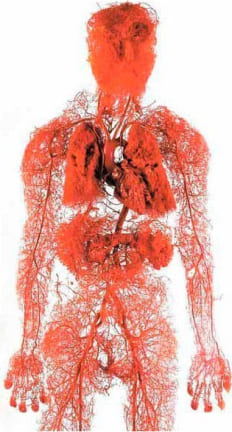

Apa organ terbesar dalam tubuh manusia? Sedikit orang yang tahu. Bahkan mahasiswa kedokteran sering salah. Mereka biasanya mengatakan otak dan hati. Yang paling terdidik mengatakan kulit. Tetapi sebenarnya organ terbesar adalah sistem vaskular kita.

Apa organ terbesar dalam tubuh manusia? Sedikit orang yang tahu. Bahkan mahasiswa kedokteran sering salah. Mereka biasanya mengatakan otak dan hati. Yang paling terdidik mengatakan kulit. Tetapi sebenarnya organ terbesar adalah sistem vaskular kita.

Untuk lebih jelasnya, panjang ekuator Bumi adalah 40.000 kilometer. Ternyata "benang" pembuluh darah dari satu orang saja bisa memeluk seluruh planet 2,5 kali.

Bukankah itu menakjubkan?

Pembuluh darah bukan hanya tabung yang mengalirkan darah. Ini adalah organ yang kompleks dan unik; ketika gagal, penyakit dapat segera muncul.

Pembuluh darah adalah sistem pemberian makan kita, hidup itu sendiri bergerak melalui pembuluh darah. Jika sebagian besar jalur terblokir, hidup akan berhenti.